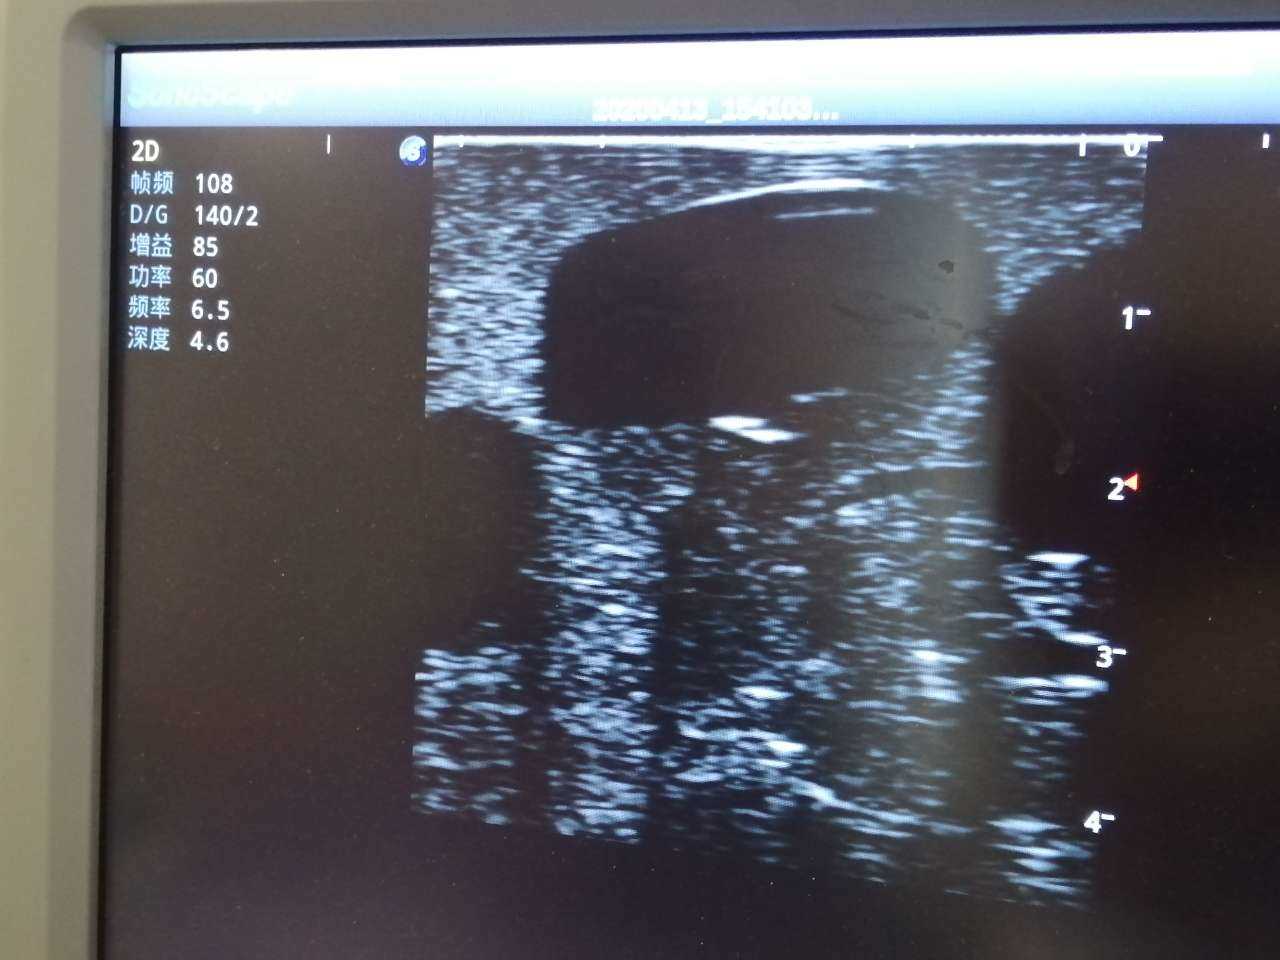

Abscess Drainage Ultrasound Trainer

Model TYE1562

The trainer is designed for abscess ultrasound recognition, drainage, surgical cutting & suturing. With realistic landmarks and high-quality images, it’s an excellent choice for abscess-related skill training and practice.

· Proper transducer positioning

· Ultrasound image interpretation

· Ultrasound recognition of abscess

· Abscess drainage

· Anatomy: accurate anatomical structures like iliac crest, cleft starting point etc.

· Different abscess types: single sac on the right side and multiple sacs on the left side

· High-quality ultrasound images to show skin, soft tissues, abscess cavity and pus

· Support abscess incision, drainage with visible fluid and suturing